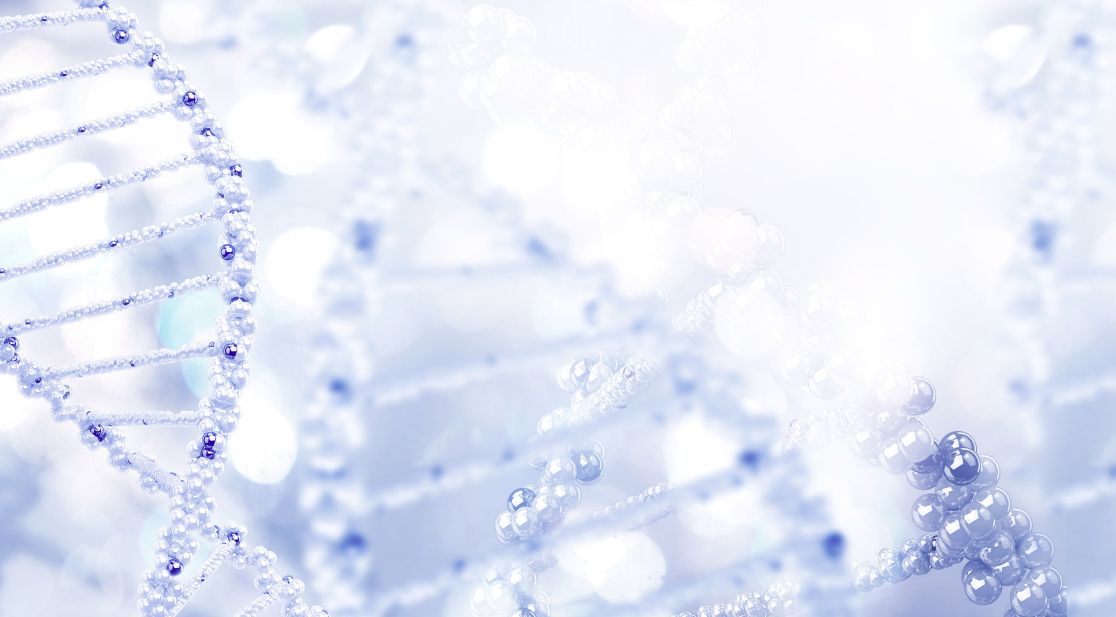

Wissenschaftliche Abbildung

PET/CT mit Darstellung der einseitig reduzierten Reservekapazität/Durchblutung (kalte Farben) im Vergleich zum physiologischen Anstieg der Perfusion auf der Gegenseite (warme Farben).

Die wichtigste Untersuchung zur absoluten Darstellung des Blutflusses im Gehirn im Ruhezustand (baseline) und nach medikamentös stimulierter Gefäßweitstellung ("Diamox/Acetazolamid-Challenge") ist das sogenannte Wasser (H2 15O) PET/CT. Bei dieser Untersuchung wird eine definierte Menge kurzzeitig radioaktives Wasser in das Blutsystem appliziert und somit kann die absolute Blutmenge im Gehirn für jedes Gefäßterritorium bestimmt werden. Dies erfolgt dann sowohl im Ruhezustand und nach Medikamentengabe. Somit kann man die cerebrale Perfusionsreserve absolut darstellen und an Hand dessen Gefäßterritorien mit benötigter Revaskularisation (Anlage eines Bypasses) identifizieren. Auf Grund des benötigten speziellen Nuklearmedizinischen Setups kann diese Untersuchung nur an wenigen Orten in Deutschland durchgeführt werden. Hierfür kooperieren wir mit der Nuklearmedizin der Universität in Freiburg.

PET-CT nach Diamox Gabe

PET-CT nach Diamox Gabe zeigt eine einseitig deutlich reduzierte Perfusionsreserve (grüne Farben) im Vergleich zur Gegenseite mit ausreichendem Anstieg der Durchblutung (warme Farben).